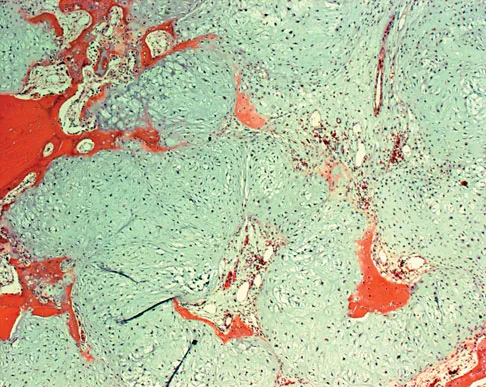

A 56-year-old woman has a painful mass on the bottom of her left foot, and orthotic management has failed to provide relief. Examination reveals that the mass is contiguous with the plantar fascia. An MRI scan shows a homogenous nodule within the plantar fascia. Resection of the tumor is shown in the clinical photograph in Figure 39. What type of cell is most likely responsible for the formation of this tumor?

Explanation